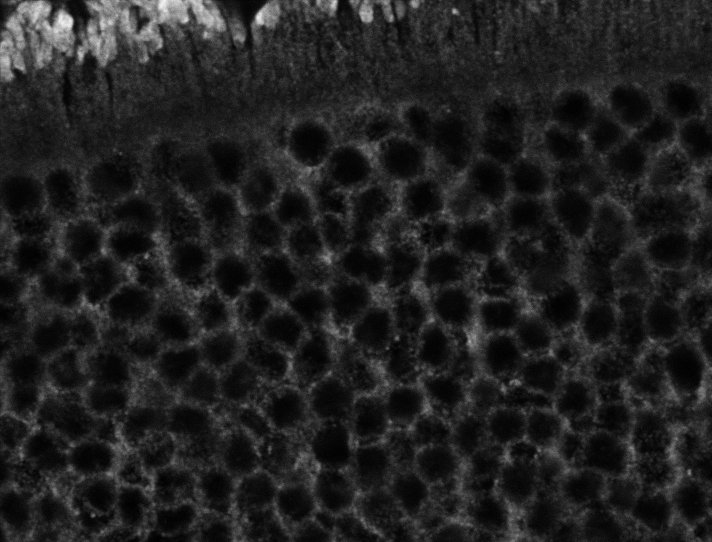

Healthy Retina

Healthy Choroid